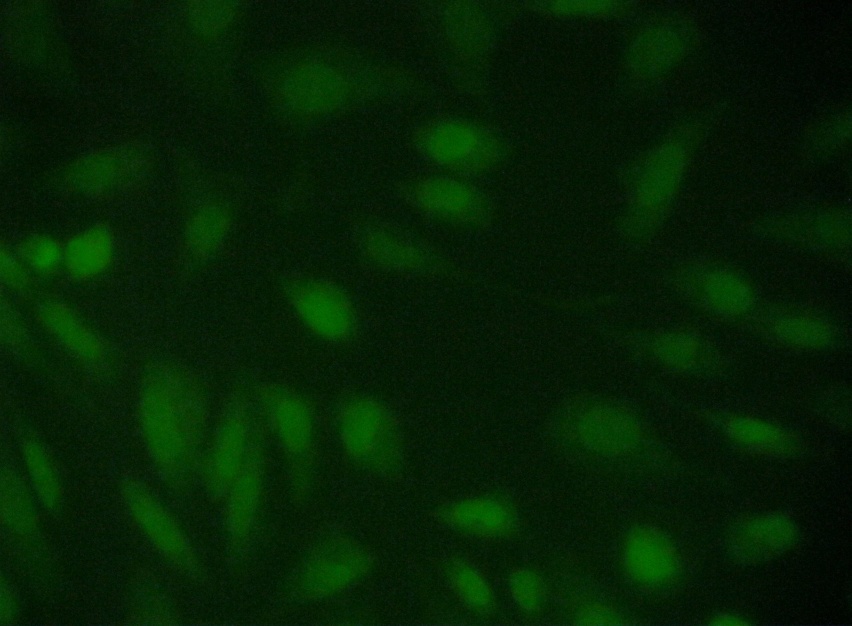

To better understand morphological change of Hep 3B cells after silver nanoparticles treatment, the cells were observed under acridine orange/ethidium bromide (AO/EB) double staining after treatment at different time points of silver nanoparticles. The figure shows. that the Silver Nanoparticles induced apoptosis after 24 and 48 hours incubation. Cells stained green represent viable cells (Figure 4a), whereas bright greenish yellow staining represented early apoptotic cells, and reddish or orange staining represents late apoptotic cells. As shown in (Figure 4b) Hep 3B cells after 24 hours treatment showed slight changes in cellular morphology, including chromatin condensation and fragmented nuclei. On the other hand, (Figure 4c) show higher number cells with increased chromatin condensation with increased fragmented nuclei thus it represents increase in the number of apoptotic cells after 48 hours of treatment.

Fig. 4a: Detection of Apoptosis Acridine orange/ Ethidium bromide Dual staining - Hep 3B cell line Control

Fig. 4b: 24 hrs after treatment of Hep 3B cell line with IC50 concentration

Therefore, using the AO/EB staining procedure, the morphological features of a Hep 3Bcell line in apoptosis were time dependent, i. e., a stronger apoptosis signal was induced with increase in the time. The cytotoxic effects of SNPs, probably due to the fact that SNPs may interfere with the proper functioning of cellular proteins and induce subsequent changes in cellular chemistry [17.18] reported a significant cytotoxicity of AgNPs in BRL 3A rat liver cells.